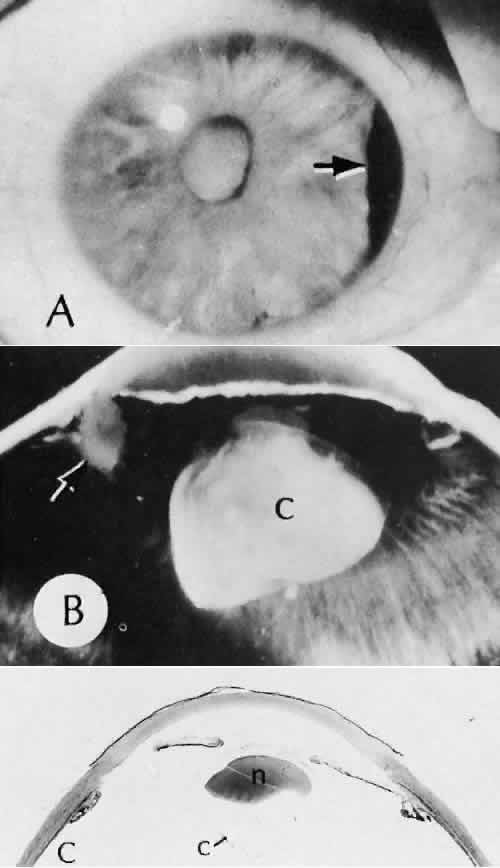

| All ocular surgical procedures are associated with potential complications. A

complication is a deviation from the natural course of the expected

tissue response after a surgical procedure and, in the case of ocular

surgery, usually results in a compromise of ocular function. Complications

may arise from the surgical procedure itself or be the result

of an aberration of the wound healing process. All surgeons will encounter

surgical complications. Eyes afflicted with severe or multiple

disease processes are more likely to develop complications. Early recognition

and a thorough understanding of these deviations from normal allow

for more effective therapeutic intervention.86 Many complications originate from so-called surgical confusion (Fig. 24). Most arise from a lack of knowledge, a lack of judgment, or problems in perception. At times, lack of attention to detail in preoperative planning may lead to a drug reaction, inadequate anesthesia, misplacement of incisions and sutures, or a patient who is unable to control a cough reflex. What is recognized histologically as the immediate cause of the problem may well have its origin in improper planning of the procedure. CATARACT EXTRACTION Intraoperative Complications Complications occurring from the time the patient enters the operating room until the patient leaves the operating room are considered intraoperative.87,88 Misplacement of an anterior segment incision too far anteriorly into the cornea may create an unacceptable degree of scarring or astigmatism, whereas misplacement too far posteriorly (Fig. 25) may cause the incision to enter the ciliary body instead of the anterior chamber, an especially serious event in glaucoma filtering procedures. Misplacement oflimbal sutures (Fig. 26) may cause anterior wound gaping if placed too far posteriorly or posterior wound gaping if placed too far anteriorly. A deep suture may enter the anterior chamber and lead to wicking and a flat anterior chamber postoperatively. A suture placed at different depths in the two sides of the wound results in faulty apposition of the wound edges. Descemet's membrane is only loosely adherent to the posterior stroma and may be stripped into the anterior chamber at the time of the corneal incision placement (Fig. 27) or injection of sodium hyaluronate. Splitting off of Descemet's membrane from the posterior cornea can lead to postoperative intractable corneal edema.89,90 Intraoperative anterior chamber hemorrhage may result from an inadvertent iridodialysis or from the iridectomy wound. The site of hemorrhage is usually found along the scleral side of the cut edge of the wound. This type of hemorrhage rarely leads to serious clinical problems.91 Rupture of the posterior lens capsule (Fig. 28) increases the risk of vitreous loss and limits options for the implantation of an intraocular lens. Retention of lens capsular tissue or vitreous in the wound (Fig. 29) will significantly delay the wound healing process. Vitreous loss leads to an increased incidence of iris prolapse, bullous keratopathy, epithelial downgrowth, stromal overgrowth, wound infection and endophthalmitis, updrawn or misshapen pupil, vitreous bands, postoperative flat anterior chamber, secondary glaucoma, retinal detachment, cystoid macular edema, optic disc edema, vitreousopacities, vitreous hemorrhage, and other sight-threatening consequences.92 Damage to the endothelium during insertion or positioning of the lens was one of the most common problems with intraocular lens implantation until the widespread use of intraoperative viscoelastics. The endothelial cell damage may manifest on the first postoperative day as corneal edema. The course of the edema may wax and wane and ultimately result in pseudophakic bullous keratopathy months or years after surgery. Detachment of Descemet's membrane, inadvertent iridodialysis, cyclodialysis, or rupture of the posterior capsule also may occur during lens insertion and positioning. Expulsive choroidal hemorrhage (Fig. 30) is a rare catastrophic complication often resulting in total loss of the eye.93 The site of hemorrhage is probably a sclerotic choroidal arteriole where the vessel crosses the suprachoroidal space from the scleral canal. The sudden hypotension after surgical penetration of the globe causes a bending and then a rupture of the arteriole.94 Although most hemorrhages are massive and immediate, they occasionally are delayed, and some may not occur for days or weeks after surgery. Delayed choroidal hemorrhage may occur at the time of corneoscleral suture removal,95 because of clinically unapparent wound dehiscence or as a result of perforation of a corneal ulcer. Histologically, massive choroidal hemorrhagic detachment is associated with a retinal detachment. The retina and choroid may herniate through the scleral wound. A ruptured ciliary artery may be found in the suprachoroidal space. Postoperative Complications Postoperative complications may arise from the time the patient leaves the operating room until approximately 6 weeks after surgery.96 A flat anterior chamber is characterized by anterior displacement of the iris to near or in actual contact with the posterior surface of the cornea. The most common cause is leakage of aqueous along one of the suture tracks. Prolonged decompression of the anterior chamber increases the risk of synechiae formation and intractable secondary closed-angle glaucoma. Corneal endothelial damage may result in bullous keratopathy. Choroidal edema (choroidal hydrops or detachment) (Fig. 31) may be associated with a flat anterior chamber and may potentiate the condition. The choroidal edema will slow or stop aqueous production by the ciliary body, further delaying reformation of the anterior chamber. The histologic characteristics of choroidal edema consist of spreading of the choroidal tissue in a fanlike configuration and eosinophilic fluid filling the intervening spaces. The edema fluid may be lost in processing, leaving multiple apparently empty spaces. Iris or lens capsular incarceration into the wound and extending to the conjunctival space (Figs. 32 and 33) may act as a wick through which aqueous can escape, causing a flat anterior chamber. Histologically, iris, which is frequently recognized only by the presence of melanocytes, is seen in the limbal scar, in the limbal episclera, or in both areas. Vitreous wick syndrome consists of vitreous incarceration in the wound, where the vitreous may extend beyond the wound to the subconjunctival space or occasionally to the ocular surface.97 Anchoring of the vitreous anteriorly in this manner may lead to extensive intraocular inflammation even in the absence of infection. The vitreous may act as a conduitfor bacteria, leading to bacterial endophthalmitis.98–100 Pupillary block glaucoma results from isolation of the posterior chamber from the anterior chamber. Occasionally, even in the presence of a clinically patent peripheral iridectomy or iridotomy, the aqueous cannot exit into the anterior chamber. The block results from contact of formed vitreous, lens remnants, or intraocular lens material with the posterior surface of the iris.101,102 The area of contact may include the iridectomy or iridotomy site. Prolonged contact with any of these tissues or materials will cause posterior synechiae formation. After complete posterior synechiae formation, peripheral anterior synechiae develop. Pupillary block glaucoma (closed-angle glaucoma) may not be clinically evident until aqueous production returns to normal levels after surgery. The intraocular lens may be a stimulus for ongoing uveitis, hyphema, and glaucoma (UGH syndrome) (Fig. 34) through multiple factors.103,104 Although lens manufacturing has improved since the early days of fabrication, retained polishing compounds or burrs and irregular surfaces of the lens or loops may cause a low-grade, sterile endophthalmitis.105 Most intraocular lens materials, with the exception of polymethylmethacrylate, have been shown to stimulate some degree of inflammation, which in turn may cause biodegradation of the lens material.106 Several epidemics of lenses contaminated with fungus have been reported. Intermittent movement or continuous pressure of the intraocular lens material against ocular tissue often will result in focal necrosis, tissue disruption, or microhyphema, which may lead to fibrous scarring. This is particularly important when the tissues of the anterior chamber angle are in contact with an anterior chamber lens. Posterior lens loops may erode the iris pigment epithelium and give rise to a type of pigmentary dispersion syndrome (Fig. 35).107,108 Lenses directly supported by the iris have caused lacerations of the iris because of continuous compression by metallic loops (see Fig. 35).109 Iris-supported intraocular lenses are associated with a high incidence of dislocation and subsequent damage to the eye. Corneal endothelial decompensation (Fig. 36) may lead to bullous keratopathy at almost any time in the postoperative period, depending on the state of health of the endothelium at the time of surgery and the extent and nature of injury to the endothelial cells.110,111 Corneal edema may present early in the postoperative period when the cornea has been compromised by advanced Fuchs corneal dystrophy. If the endothelial cells are healthy and the intraoperative trauma is minimal, the signs of decompensation may not appear for decades. Endothelial damage may be the result of mechanical contact with surgical instruments or an intraocular lens, a toxic reaction to solutions used intraoperatively, poor tissue handling techniques, or prolonged and intensive postoperative inflammation.112 Histologically, the corneal epithelium is generally thinned. There may be areas of intraepithelial basement membrane and cyst formation, resulting from malorientation of the squamous epithelial cells during recovery from multiple episodes of bullous separation from Bowman's membrane (Fig. 37). Bullous separation of the epithelial cells varies in extent but is almost always present. Focal areas of interruption of Bowman's membrane and anterior corneal stroma scarring will mark rupture of bullae and subsequent ulceration. In chronic cases, extensive degenerative pannus formation is often seen. The corneal stroma may show a decreased density of keratocyte nuclei. A decrease in or absence of the artifactual clefts of the corneal stromal lamellae suggests edema of the stroma. Descemet's membrane may be focally or diffusely thickened with preexisting Fuchs corneal dystrophy (Fig. 38). In most cases, Descemet's membrane is normal in character and thickness. Often the corneal endothelial density is reduced to the point that only an occasional endothelial cell nucleus can be seen. Infectious bacterial endophthalmitis (Figs. 39 and 40) usually presents early in the postoperative period.113,114 Pseudomonal and streptococcal organisms often cause rapid and total destruction of the eye. Organisms of especially low virulence, such as Staphylococcus epidermidis and Priopionibacterium acnes, may not present for months and may be misinterpreted as sterile endophthalmitis caused by a toxic reaction to intraocular lens materials or phacoanaphylactic endophthalmitis targeted to lens cortical remnants.115–117 Infectious endophthalmitispresenting months after surgery may be caused by a fungal infection or by bacteria of low virulence as pointed out above. Delayed Complications Delayed complications are those that occur more than 6 weeks after surgery. These complications include corneal endothelial decompensation and delayed infectious endophthalmitis, as discussed previously. Elschnig's pearls (Fig. 41) result from aberrant attempts by lens cells attached to the lens capsule to form new lens “fibers.” Histologically, large, clear lens cells (“bladder cells”) are present behind the iris, in the pupillary space, or in both areas. Soemmerring's ring cataract results from the loss of anterior and posterior cortex and nucleus but with retention of equatorial cortex. Apposition of the central portions of the anterior and posterior lens capsule causes a doughnut configuration. Frequently, the doughnut is not complete, so that C- or J-shaped configurations result. Histologically, two balls of trapped and proliferated lens cells are encapsulated behind the iris leaf and connected by adherent anterior and posterior lens capsule in the form of a dumbbell.118 Delayed complications of intraocular lenses themselves are infrequent. The incidence of posterior capsular opacification ranges between 11% and 46% in this period, apparently lower in the presence of an intraocular lens than with extracapsular cataract surgery alone.119,120 Histologically, residual lens epithelial cells are transformed into cells with myofibrillar contractile properties, which wrinkle and opacify the posterior capsule and synthesize the extracellular matrix. Retinal detachment (Fig. 42) occurs in approximately 2% to 8% of intracapsular cataract surgeries, compared with approximately 0.0013% in the general population. The incidence of retinal detachment after extracapsular cataract extraction and posterior chamber lens implantation ranges between 0.6% and 1.5%.121 Vitreous loss increases the incidence of postoperative detachments, particularly if there is vitreous incarceration into the cataract wound. The character of the retinal detachment is independent of the type of cataract surgery or the type of intraocular lens implanted. However, a lower incidence of proliferative vitreoretinopathy appears in cases of extracapsular cataract extraction than was formerly seen with intracapsular cataract extraction. Aphakic or pseudophakic glaucoma122,123 is a nonspecific term referring to a pathologic and sustained increase in pressure after surgery for removal of cataract. In the delayed phase, this glaucoma is mainly caused by secondary chronic angle closure. However, a preexisting predilection to simple open-angle glaucoma may be the cause. Circumferential peripheral anterior synechiae may develop from persistent flat anterior chamber. Focal synechiae are often found adherent to the posterior aspects of the surgical incision. Histologically, the iris is apposed to the posterior cornea, often central to Schwalbe's ring. Posterior synechiae are generally the result of posterior chamber inflammation (caused by iridocyclitis, endophthalmitis, or hyphema) causing iris bomb, and secondary peripheral anterior synechiae (Fig. 43). Histologically, the posterior pupillary portion of the iris is adherent to the anterior face of the vitreous, to the lens remnants, to the intraocular lens, or to all three structures. The anterior peripheral iris is adherent to the posterior cornea (peripheral anterior synechiae), frequently central to Schwalbe's ring. Epithelial downgrowth (ingrowth) (Fig. 44) is one of the most serious causes of pseudophakic glaucoma, in which surface epithelium (probably from the conjunctiva) grows into the anterior chamber. This condition is more likely to occur with fornix-based conjunctival flaps than with limbus-based flaps and in eyes with problems in wound closure, such as vitreous loss, wound incarceration of tissue, delayed reformation of the anterior chamber, or frank rupture of the limbal incision, and when instruments such as iridectomy forceps are contaminated with surface epithelium before they are introduced into the eye. Epithelial downgrowth causes an anterior chamber angle closure by means of peripheral anterior synechiae or lines an open anterior chamber angle and obstructs aqueous outflow mechanically. Histologically, the epithelium is seen to grow most luxuriously and in multiple layers on the iris where there is a good blood supply, but it tends to grow sparsely and in a single layer on the posterior surface of the avascular cornea. The epithelium may extend behind the iris, over the ciliary body, and even far into the interior of the eye. Iris cyst formation (Figs. 45 and 46 is also caused by implantation of surface epithelium onto the iris at the time of surgery or trauma. The cyst generally grows slowly and is accompanied by peripheral anterior synechiae. If extensive, the cysts may cause a secondary chronic closed-angle glaucoma. Histologically, the cyst is lined by stratified squamous or columnar epithelium, sometimes containing mucous cells, and is filled with keratin debris (white or pearly cysts) or mucous fluid (clear cysts). Stromal overgrowth (Fig. 47) is a condition characterized by growth of fibrous connective tissue into the anterior chamber. It is most likely to occur after vitreous loss or tissue incarceration into the surgical wound. The overgrowth may be localized, may be limited to the area of surgical perforation of Descemet's membrane, or may be extensive. When overgrowth is extensive, peripheral anterior synechiae and secondary closed-angle glaucoma result. As with epithelial downgrowth, the stromal overgrowth may extend behind the iris, over the ciliary body, and far into the interior of the eye. Histologically, fibrous tissue generally extends from the corneal stroma or is in continuity with it, through a large gap in Descemet's membrane. The fibrous tissue often covers the posterior cornea, fills part of the anterior chamber, occludes the anterior chamber angle, and may extend into the vitreous compartment to attach posteriorly onto the retina. Bacterial inflammation is rare in the delayed period after surgery, except after filtering procedures in which bacteria can gain access to the inside of the eye by way of the bleb (Fig. 48). Another exception to this rule is Priopionibacterium acnes or Staphylococcus epidermidis endophthalmitis, which infects lens remnants and may not clinically manifest for many months after cataract extraction. Fungal endophthalmitis (Fig. 49) may take the form of keratitis or endophthalmitis. Histologic characteristics of end-stage endophthalmitis include fibrovascular organization centered about a chronic nongranulomatous inflammatory reaction contiguous with lens remnants, causing cyclitic membrane formation and retinal detachment. Multiple small foreign bodies, inadvertently introduced at the time of surgery, can cause a delayed chronic nongranulomatous or granulomatous inflammatory reaction. Phacoanaphylactic endophthalmitis or sympathetic uveitis may occur after extracapsular cataract extraction (discussed elsewhere in these volumes). Healed cataract wounds may rupture because of trauma. In particular, blunt trauma to the eye may cause ocular rupture, often at the site of a cataract scar that remains weaker than surrounding tissue. Cystoid macular edema, or Irvine-Gass syndrome, is an inflammatory, degenerative condition of unknown cause that involves primarily the macula and leads to temporary or permanent loss of macular function. This condition can occur anytime after cataract surgery (even up to 5 years), but most cases occur within 2 months of surgery. The initial clinical sign is a sudden decrease in visual acuity. At least 50% of the cases are self-limiting, and the macular edema resolves completely, with or with-out therapy, within 1 year. Most patients experi-ence spontaneous recovery of vision. In a few cases,however, the intraretinal edema may persist, andsecondary permanent complications, such as lamel-lar macular hole formation, may occur. The condi-tion can be precipitated or aggravated by topicalepinephrine therapy for glaucoma. The cause ofcystoid macular edema is unknown, but in somecases (probably the minority), vitreous traction or aposterior vitritis may play a role (Fig. 50). Histo-logically, iritis, cyclitis, retinal phlebitis, and retinal periphlebitis have been noted. Whether these conditions cause the cystoid macular changes or are simply incidental findings in enucleated eyes is not clear. A lamellar macular hole may occur as a permanent complication. Ophthalmoscopically (best seen with a slit-lamp biomicroscope), multiple (usually four or five) intraretinal microcysts are seen in the macular area, obscuring the normal foveal reflex. The cysts fill early with fluorescein, and pooling causes a characteristic stellate geometric pattern that persists for 30 minutes or longer. Granular fluid is seen in the microcystic spaces (Fig. 51). The anatomic basis of early cystoid macular edema probably is edema of Müller cells; later, Müller cell membranes break down and the edema becomes extracellular. PENETRATING KERATOPLASTY Immediate Complications Complications of penetrating keratoplasty may arise in the selection of donor material. The success of a graft depends on the health and integrity of the donor endothelium. Compromise of endothelial function attributable to the age of the donor, preexisting endothelial disease (Fuchs corneal dystrophy), toxicity of storage procedures, microbial infection, or intraoperative trauma will lead to early endothelial decompensation. Immunologic testing and a careful history of infectious disease of the donor (AIDS, hepatitis, Jakob-Creutzfeldt disease, and rabies) are essential because the virus may be harbored in the donor tissue. Retention of significant amounts of host Desce-met's membrane and presence of nonviable peripheral host tissue in patients with alkali burns are additional potential intraoperative problems. Improper apposition of the donor-host interface may lead to multiple structural and refractive problems. Overriding of the wound edge is a likely site for wound leak, leading to a flat anterior chamber, which in turn may lead to central anterior synechiae to the wound or total anterior synechiae. Malposition of the posterior wound edge is likely to enhance fibrous tissue proliferation, which may remain in the local region of wound or may spread peripherally or even centrally (stromal in growth). Postoperative Complications Penetrating keratoplasty has the same risks for microbial infection, epithelial ingrowth, stromal ingrowth, and expulsive choroidal hemorrhage, as does anterior segment surgery in general. Immune rejection of a corneal graft is an unusual complication, except when the host tissue is extensively vascularized. Immune stromal graft rejection clinically manifests 2 to 3 weeks postoperatively and is heralded by inflammatory signs associated with progressive vascularization of the graft. Histologically, a central necrotic area is bounded peripherally by a zonal inflammatory response. Polymorpho-nuclear leukocytes predominate near the necrotictissue, surrounded by a zone of lymphocytes and plasma cells. The endothelial layer may undergo specific graft rejection. This is recognized clinically as a centrally advancing, linear, posterior corneal opacity (Khoudadoust's line). Histologically, there is a chronic nongranulomatous inflammatory reaction about necrotic endothelial cells. Delayed Complications Graft failure is a nonspecific term used to indicate progressive or persistent opacification of a donor cornea. In most cases, the histologic characteristics are those of corneal endothelial decompensation. In some cases, particularly those with underlying systemic disease or ocular surface abnormalities, there may be extensive corneal ulceration or perforation. REFRACTIVE SURGERY Immediate Complications Accidental perforation of the globe is possible with any of the refractive procedures. Variability of the incision depth is one of the most important factors in the ultimate variability of the refractive correction obtained by the procedure. Postoperative Complications Microbial endophthalmitis, even leading to blindness, has been reported as a complication of this type of procedure. There appears to be an acute postoperative endothelial cell loss that is not progressive. Wound healing of radial keratoplasty has been complicated by intrastromal epithelial cyst formation and a generalized decrease in the rate of healing of the incision (Fig. 52). Complete healing and refractive stability may not be realized for years. Epikeratophakia procedures have been complicated by delayed reepithelialization of the grafted tissue and epithelial retention or proliferation along the interface between the lenticule and the host tissue. Persistent folding of Bowman's membrane underlying the grafted tissue and abnormal keratocytes in the underlying recipient stroma may lead to a poor visual result. In some cases, the lenticule of keratomileusis has been slow to be repopulated by host keratocytes, which may be responsible for persistent opacification of the grafted area. Thickening of the epithelial basement membrane, a decreased density in hemidesmosomes, and abnormalities of Bowman's membrane have been observed. Abnormal proteoglycan synthesis also has been suspected in these cases. Visually significant opacities at the tissue-synthetic material interface have been noted with corneal intrastromal inlay procedures (Fig. 53). This material, which has been found to contain lipid, appears to accumulate over time. Corneal inlays of all types have been complicated by necrosis of the tissue overlying the pocket and extrusion of the synthetic material. Delayed Complications An early type of radial keratotomy, which included incisions of the internal surface of the cornea, has resulted in a high degree of corneal endothelial decompensation 20 years after the procedure, regardless of the age of the patient at the time of surgery. LASIK Complications of LASIK Variability in actual flap thickness has also been noted in several studies. The lack of uniformity of flap dimensions may be important in repositioning the flap in the stromal bed.124 Microfolding of the anterior corneal flap was found in 94% of eyes examined by confocal microscopy. The folding was attributed to stretching of the tissue during laminectomy or to imprecise registering of the flap tissue with the lamellar bed.75 The character of the blade edge, particularly of a blade that has been used for more than one procedure, also influences the morphology of the stromal incision. Notching of the blade profile with repeated use has been observed by scanning electron microscopy. Notching of the blade edge also appears to be associated with accumulation of tissue remnants on the surface of the blade.67,68 The tissue remnants can be identified as reflective interface particles by confocal microscopy. Potential sources of the material include metal from the microkeratome blade, cotton, lipid, inflammatory cells, intact epithelial cells, or remnants.75 Complications occur in approximately 3% to 5% of LASIK procedures.78,125,126 Intraoperative compilations are primarily related to creation of the lamellar flap. Included among this type of complication are flap irregularities, epithelium and other material within the lamellar interface, regular and irregular astigmatism, flap loss, displacement, and button-holing. Infection is a rare but potentially serious complication.78,127–131 Perforations of the globe have been described.132–137 Potential complications at 6 months include epithelial ingrowth, corneal flap melting, decentered ablation, and irregular astigmatism with loss of best-corrected visual acuity.124 Complications related to abnormal endothelial cell function have been infrequent.134,138–140 Progressive epithelial ingrowth may occur characterized as a continuous sheet of epithelium contiguous with the flap edge (Fig. 54).124,141 Epithelial ingrowth into the intrastromal interface may be associated with enzymatic digestion of the cornea.142 Diffuse interface keratitis is a condition char-acterized by acquired opacification at the level ofthe intralamellar bed after a LASIK procedure(Fig. 55).143 Many causes of the syndrome have been reported144–147 and include exotoxins released from sterilizer reservoir biofilm148 and debris on the microkeratome blade149 and methylcellulose sponge material.150 Most cases resolve spontaneously.151 The resistance of eyes to trauma after LASIK, even in the absence of healing appears to be similar to unoperated human eyes as evaluated in a model of postmortem refractive procedures performed on autopsy eyes.152 In this model, radial keratotomy incisions predisposed rupture at lower energy levels than in unoperated eyes.153 Postoperatively, there was a decrease in intraocular pressure measured by central tonometry that was statistically significant. Differences in pneumotonometry were less substantial, with greater reliability of pneumotonometry than Goldmann applanation tonometry after LASIK.154 GLAUCOMA SURGERY Immediate Complications Creation of a button hole in the conjunctiva is not serious in cataract surgery but may lead to failure in filtering procedures. Misplacement of the incision too far posteriorly may cause the incision to enter the ciliary body instead of the anterior chamber, an especially serious event in glaucoma filtering procedures. Postoperative Complications Cataract formation may be caused or accelerated by glaucoma surgery, even if the lens is not apparently damaged by physical contact. The cataract may be a result of shunting of the aqueous through the iridectomy, so that the anterior and posterior surfaces of the lens are not properly nourished. Bacterial endophthalmitis may occur. Hypotony and choroidal detachment have complicated trabeculectomy procedures more common with full-thickness filtering procedures. Seton devices have been complicated by conjunctival erosion by the synthetic parts, blockage of the proximal orifice, corneal decompensation, extrascleral tube compression, and blockage of the distal orifice. Delayed Complications Procedures to lower intraocular pressure function by transconjunctival filtration, absorption of aqueous into the subconjunctival vessels, recanalization, reopening of drainage channels, passage through areas of perivascular degeneration, or any combination. Incorrect placement of the incision, hemorrhage, inflammation, prolapse of the intraocular tissue into the filtration site, dense fibrosis, peripheral anterior synechiae formation and secondary chronic closed-angle glaucoma, and endothelialization of the bleb may cause filtration failure. The histology depends on the underlying cause. Even in the delayed period, bacteria may gain access to the interior of the eye, by way of the bleb, and cause endophthalmitis. RETINAL REATTACHMENT SURGERY Intraoperative Complications A misplaced implant, explant, or scleral suture can lead to an improper scleral buckle or premature drainage of the subretinal fluid. Misplaced, insufficient, or excessive diathermy or cryotherapy can cause unsatisfactory results by not closing the retinal hole. Cut or obstructed vortex veins can lead to choroidal detachment or hemorrhage (Fig. 56), which is most often caused by hypotension induced by surgical drainage of subretinal fluid. Overuse of scleral cryotherapy or diathermy also may be a cause. Other causes include cutting or obstruction of vortex veins and incision of the choroidal vessels at the time of surgical drainage of the subretinal fluid. Retina may be incarcerated in a surgical drainage site. Acute closed-angle glaucoma may be the result of the buckling procedure, especially if unaccompanied by drainage of the subretinal fluid or anterior chamber paracentesis. If the glaucoma is not recognized, central retinal artery occlusion may occur and result in blindness. Postoperative Complications The original retinal hole may remain open, or a new one may develop or be missed preoperatively. Choroidal detachment and choroidal hemorrhage also may occur during this time. Acute or subacute scleral necrosis (Fig. 57) may follow retinal detachment surgery after days or weeks and is probably caused by ischemia rather than infection. In the acute form, the clinical picture generally starts a few days after surgery and may resemble a true infectious scleritis but without pain. There is a sudden onset of congestion, edema, and a dark red or purple appearance of the tissues over the implant or explant. Discharge is not marked or is absent altogether. The vitreous over the buckle generally becomes hazy but may be clear. The cornea remains clear but the involved area of the sclera becomes completely necrotic. In the subacute form, the clinical picture starts with pain approximately 2 to 3 weeks after surgery. The globe may be congested but no discharge occurs. The vitreous over the buckle may be hazy or clear. The sclera in the region of the buckle is necrotic. Infection in the form of scleral abscess, endophthalmitis, or keratitis may be secondary to bacteria or fungi and is characterized by redness of the globe, discharge, and pain (Fig. 58). Anterior segment necrosis (Fig. 59) is thought to be secondary to interruption of the blood supply to the iris and ciliary body, usually by temporary removal of one or more rectus muscles during surgery. Encircling elements, lamellar dissection implants, explants, and cryotherapy or diathermy may also cause compromised blood supply. Clinically, keratopathy and intraocular inflammation usually develop in the first postoperative week. Corneal changes consist of striate keratopathy and corneal edema with epithelial bullae. Chemosis, anterior chamber flare and cells, large keratic precipitates, and white deposits on the necrotic lens capsule characerize intraocular inflammation clinically. The clinical findings are often mistaken for an infectious endophthalmitis. Later, the pupil becomes dilated. Shrinkage of the iris toward the side of the greatest necrosis and hypoxia results in an irregular pupil. Cataract, hypotension, ectropion uveae, and finally phthisis bulbi develop. A high incidence of anterior segment ischemic syndrome is seen after scleral buckling procedures in patients with hemoglobin sickle cell disease. In hemoglobin sickle cell disease, the increased frequency of anterior segment necrosis is most likely related to the increased blood viscosity and tendency toward erythrocyte packing that is found in these patients, especially those with a decreased oxygen tension. Histologically, ischemic necrosis of the iris, ciliary body, and lens epithelial cells is present, frequently only on the side of the surgical procedure. Hemorrhage in the postoperative period may be caused by a delayed expulsive choroidal hemorrhage that most probably results from necrosis of a blood vessel induced by the original diathermy or cryotherapy or to erosion of an implant or explant. Acute closed-angle glaucoma probably occurs after a retinal detachment procedure in which an encircling element or a high buckle is created. Acute closed-angle glaucoma occurs in approximately 4% of scleral buckling procedures. The pathogenesis of the angle closure is not known, although pupillary block or swelling of the ciliary body is a proposed mechanism. The buckle decreases the volume of the vitreous compartment, displacing the vitreous and lens-iris diaphragm anteriorly. Corneal edema on the first postoperative day, especially if accompanied by ocular pain, should be considered glaucomatous until proved otherwise. Histologically, the anterior displacement of intraocular structures results in encroachment of the iris on the anterior chamber angle and resultant closed-angle glaucoma. Chronic simple glaucoma may become apparent when the hypotension of a retinal detachment is alleviated by surgery. Delayed Complications Vitreous retraction by itself is of little importance, but when it is associated with fibrous or glial membranous proliferation on the internal or external surface of the retina, it can cause retinal detachment with or without retinal hole formation. Prolifera-tive vitreoretinopathy is extensive cellular prolif-eration (glial cells, retinal pigment epithelial cells,fibroblasts, and Müller cells) on retinal tissue asso-ciated with a total retinal detachment. The mem-branes distort the surface of the retina to cause a cel-lophane appearance and extend to form star foldsand other configurations of fixed retinal folds. His-tologically, fibroglial membranes can be seen onthe internal or external surface of the retina. With contraction of the myofibroblasts of the membranes, the architecture of the retina will be markedly distorted.155 An implant or explant may migrate externally along the surface of the globe and through the conjunctiva or internally into the globe (Fig. 60). Internal migration may cause hemorrhage, retinal detachment, or infection. In this setting, the conjunctival epithelium may gain access to the interior of the eye. The resultant conjunctival epithelial ingrowth complicates an already compromised eye. Retinal tacks also may migrate as far as the anterior chamber. A retinal hole may develop de novo or secondary to obvious vitreous pathology. Other late problems include heterophoria, disturbances of lid position, and secondary glaucoma (hemolytic, closed angle from prolonged or recurrent inflammation, or neovascular associated with retinal ischemia). Macular degeneration and puckering may occur if cryotherapy or diathermy has been used. |